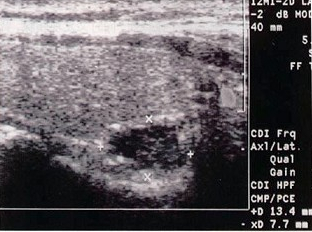

18、单项选择题

患者多处骨折,结合颈部超声图像,最可能的诊断是()